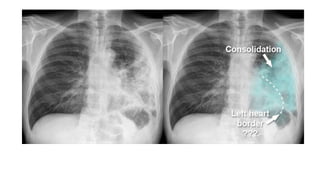

• Chest xray

• #16 Cough (with or without sputum production), dyspnea, and pleuritic chest pain are among the most common symptoms associated with CAP. Signs of pneumonia on physical examination include tachypnea, increased work of breathing, and adventitious breath sounds, including rales/crackles and rhonchi. Tactile fremitus, egophony, and dullness to percussion also suggest pneumonia. These signs and symptoms result from the accumulation of white blood cells (WBCs), fluid, and proteins in the alveolar space. Hypoxemia can result from the subsequent impairment of alveolar gas exchange. On chest radiograph, accumulation of WBCs and fluid within the alveoli appears as pulmonary opacities